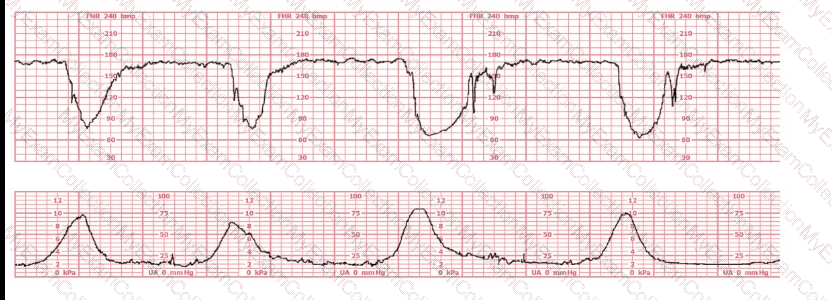

The decelerations seen in the fetal monitoring tracing shown are best described as: